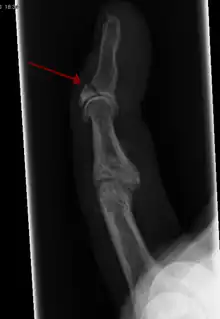

| Avulsion fracture of the proximal middle phalanx on the palm side | |